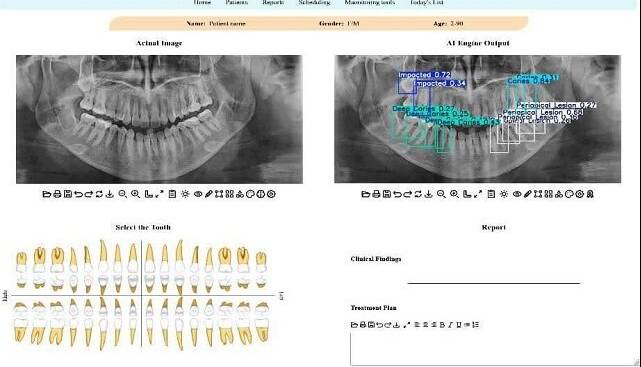

استاد دانشکده مهندسی برق و کامپیوتر دانشگاه تهران با بیان اینکه در این پژوهش جدید محققان تلاش کردهاند تا این چالش را با کمک فناوری حل کنند، افزود: برای این منظور یک سامانه تشخیصی مبتنی بر هوش مصنوعی طراحی شده است که این سامانه، معماری پیشرفته شبکه عصبی به نام YOLOv11 است که آموزش آن بر روی یک مجموعهداده عمومی انجام شده است. این مدل قادر است بهصورت خودکار، محل دقیق ضایعات و ناهنجاریها را در تصویر شناسایی کرده و احتمال درستی تشخیص خود را نیز اعلام کند.

ظروفی یکی از نقاط قوت این پژوهش را کاربردی شدن پژوهش در قالب یک اپلیکیشن وب، عنوان کرد و گفت: یکی از نقاط قوت این پژوهش، کاربردی بودن آن است. این مدل در قالب یک اپلیکیشن تحت وب پیادهسازی شده تا دندانپزشکان و رادیولوژیستها بتوانند به سادگی از آن استفاده کنند. این سامانه با مشخص کردن محل دقیق مشکلات، به پزشک در اولویتبندی و تصمیمگیری سریعتر کمک میکند.